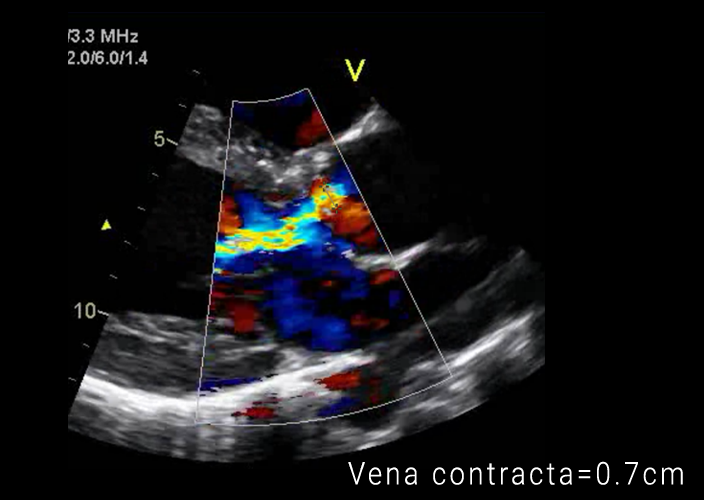

Moderate to severe aortic stenosis image This image illustrates Moderate to severe aortic stenosis.